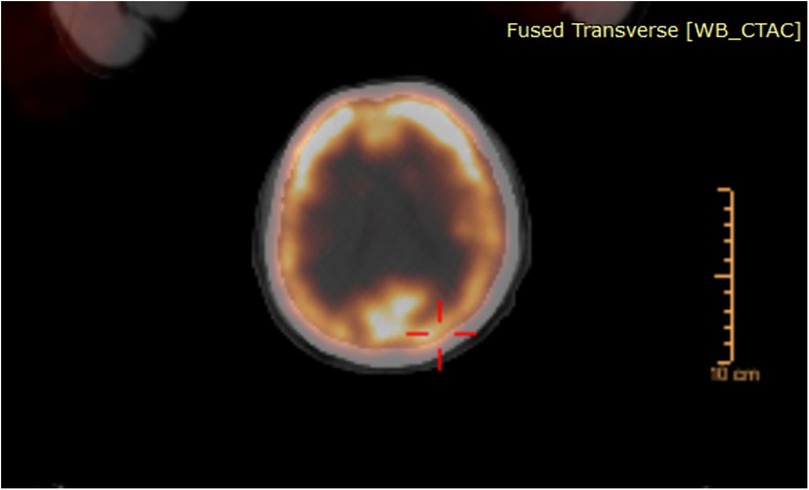

At his most recent follow-up visit, the patient reported weight loss and newly developed left-sided weakness. He had lost 15 kg over the past 6 months. Neurological examination revealed left-sided hemihypoesthesia, with upper extremity hemiparesis graded at 3/5 and lower extremity hemiparesis at 4/5. Cranial MRI demonstrated a tumoral mass in the right frontoparietal region measuring 70 mm × 50 mm × 55 mm. The lesion appeared hypointense on T1-weighted images and hyperintense on T2-weighted images, with rim-like contrast enhancement. The central portion of the lesion showed no enhancement and appeared necrotic and cystic with hypointense characteristics. The lesion was associated with surrounding edema and caused a 5 mm shift of the midline (Figures 4A,B). Based on these radiological findings and the new clinical presentation of hemiparesis, the lesion was initially considered to be intraaxial, prompting immediate surgical intervention. A neuronavigation-guided right frontoparietal craniotomy was performed. Upon opening the dura, the tumor was identified as extraaxial, with partial attachment to the dura. It was noted to be highly vascularized. Using the tumor's cleavage plane, it was carefully dissected from adjacent neural structures and internally debulked in a stepwise manner. Total resection was achieved with the assistance of neuronavigation and intraoperative ultrasound. The patient was monitored postoperatively in the intensive care unit without any new neurological deficits. Early postoperative MRI confirmed complete removal of the tumor (Figures 4C,D). Following 4 additional days of inpatient care, the patient was discharged from the hospital with no neurological deficits.

MRI images display brain scans at various angles and sections. The top row reveals abnormalities on one side of the brain, evident in both coronal and sagittal views. The bottom row shows comparative scans with clearer images of the brain's interior, some marked with yellow lines for reference. Each section highlights different details pertinent to medical analysis.

Figure 4. Preoperative cranial MRI (A,B) showed a tumoral lesion located in the right frontoparietal region measuring 70 mm × 50 mm × 55 mm, hypointense on T1-weighted and hyperintense on T2-weighted images, with rim-like contrast enhancement. The central areas of the tumor did not enhance with contrast and appeared necrotic and cystic with a hypointense signal. The lesion caused peripheral edema and a 5-mm midline shift. Early postoperative cranial MRI (C,D) confirmed total tumor resection.

Histopathological analysis showed physaliphorous cells with clear or multivacuolated cytoplasm arranged in chordoid, solid, trabecular, and pseudoglandular patterns within a myxoid stroma. The tumor stained positive for CK AE1/AE3, brachyury, and INI-1, with weak S-100 staining observed in a small number of cells. The MIB-1 labeling index was measured at 20%. These findings were consistent with a diagnosis of chordoma. The patient was placed under close clinical surveillance. One year after the surgery, no recurrence was detected, and the patient remains clinically and radiologically stable.